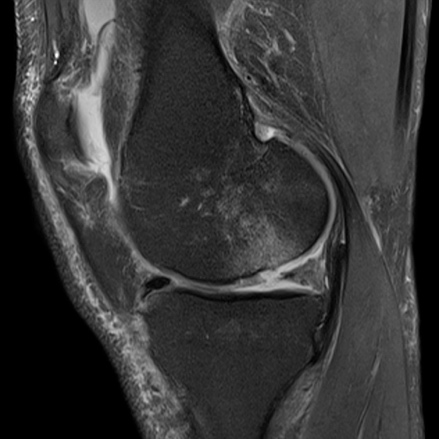

Khớp gối: Nhiều chuỗi xung 3D cho độ phân giải rất cao, hiển thị sụn viền rõ cùng nhiều chương trình giúp đánh giá thoái khớp khớp sớm

Hình 16. Hình ảnh MRI khớp gối